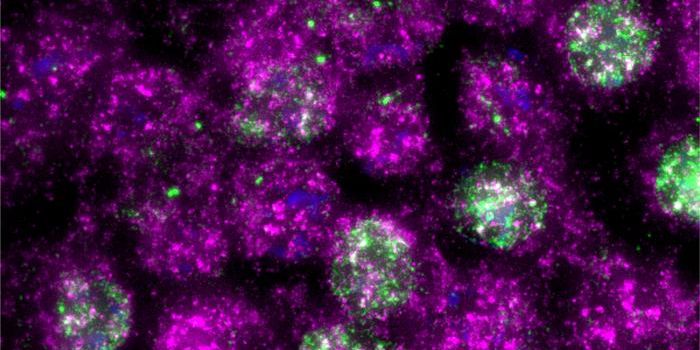

FEB 13, 2025ImmunologyImmunotherapy has changed the way physicians treat cancer patients. This approach to therapy targets the immune system t ...

FEB 09, 2025CancerGlioblastoma (GBM), an aggressive form of cancer that grows in the brain or spinal cord, occurs at an incidence rate of ...

DEC 22, 2024CancerTriple-negative breast cancer (TNBC) remains one of the most aggressive types of breast cancer. Determined by a la ...

DEC 09, 2024CancerCancer cells have evolved sophisticated strategies to evade the immune system, prolonging their survival and growth.&nbs ...

DEC 02, 2024CancerImmunotherapies have shaped the cancer research space over the past decade, proving effective for the treatment of some ...